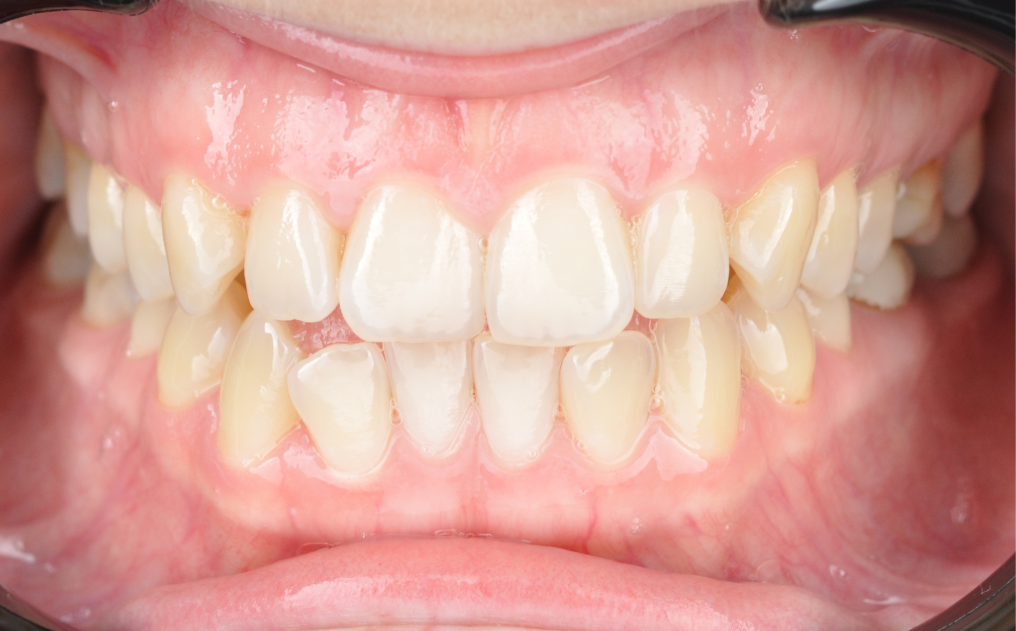

Результаты комплексного лечения

Комплексный подход команды «Архитектор Улыбок» дал закономерный результат, который был спрогнозирован еще

до старта лечения.

Здоровая улыбка

Ушел дискомфорт в суставе, исчезли боли в процессе жевания. Нижняя челюсть заняла стабильное, физиологичное положение.

Восстановилась функция

Качество жевания кардинально повысилось, процесс приема пищи снова стал комфортным.

Эстетика

Исправлен прямой прикус, восстановлена форма резцов, а улыбка стала не только красивой, но и здоровой с точки зрения биомеханики.